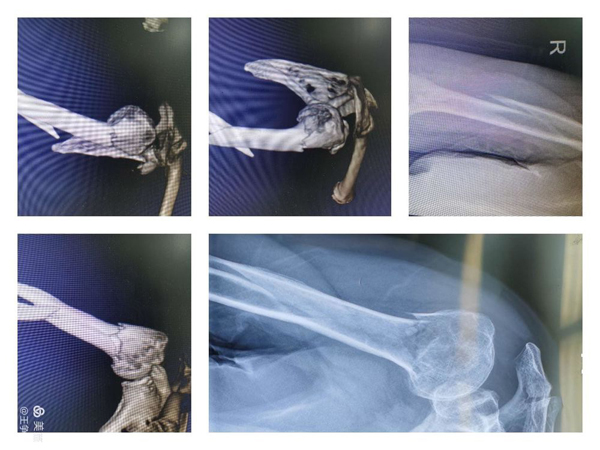

图片为术中透视及术后外观照。

近日,陕健医二一五医院骨科医院创伤骨科收治了一例高龄肱骨多段骨折的病人。83岁的女性患者因跌倒致肱骨外科颈、肱骨干粉碎骨折。入院后在和患者家属反复沟通后,决定行右肱骨骨折的复位及内固定手术。但是由于患者骨折比较特殊,按照以往的治疗方法,需要对肱骨近端和肱骨干分别进行处理,需要两套内固定器材,这使患者的创伤及经济压力都大大增加。

针对患者具体情况,郭永良主任带领科室医师团队反复讨论,最终选择了一种相对简单、微创、并且比较经济的治疗方法——肱骨“专家级”髓内钉,俗称“降落伞”髓内钉对患者进行手术。这种特殊的髓内钉设计独特,能有效固定这种多段粉碎骨折,其远端和近端有多枚、多方向不同的锁定孔,可根据骨折的具体情况进行选择使用。

手术由王争刚主任医师、吴超副主任医师主刀,在全身麻醉下进行,考虑到肱骨干部骨折位于中下段,闭合复位困难,并且有桡神经损伤风险,故术中干部骨折予以有限切开、确保桡神经安全,肱骨外科颈骨折完全闭合操作,避免影响对骨折断端血液循环,将大大缩短骨折愈合时间。

通过一套内固定器械,完成多段复杂骨折,并且全程在微创理论指导下进行,目前患者已经下地活动,术后恢复效果良好。